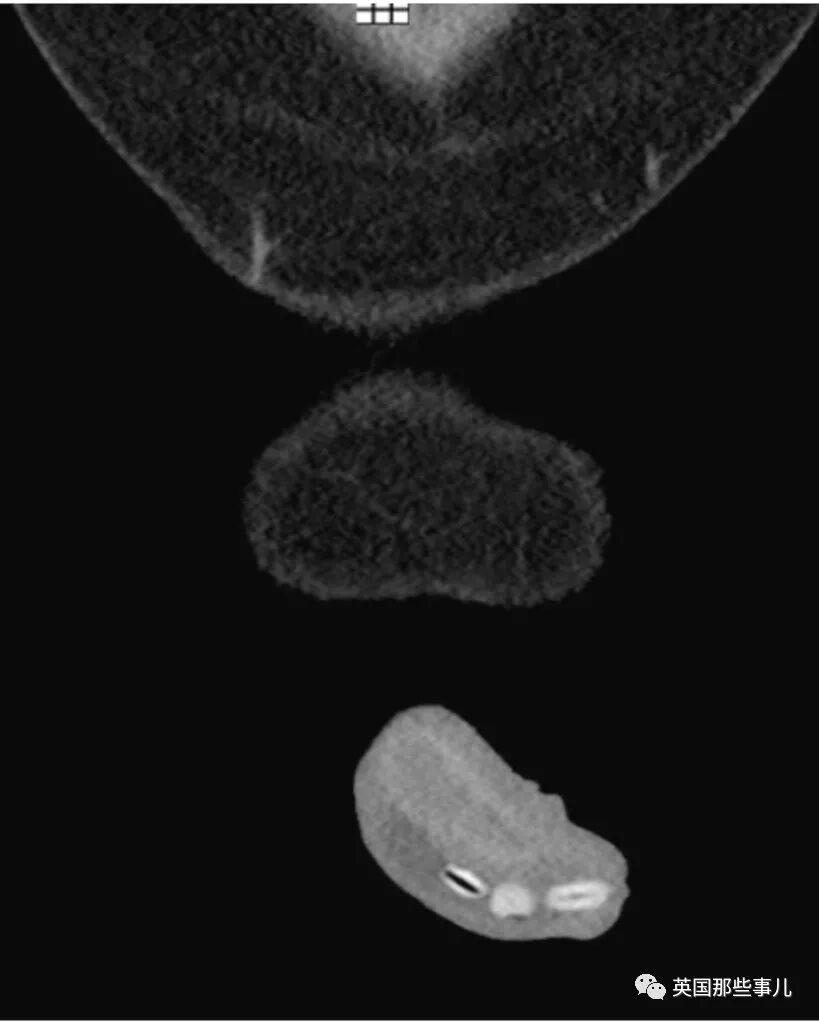

毁三观!想变“豌豆射手”,男子竟将6颗芸豆塞入......结果悲剧了 | 睡前嘿嘿嘿

湖北经视